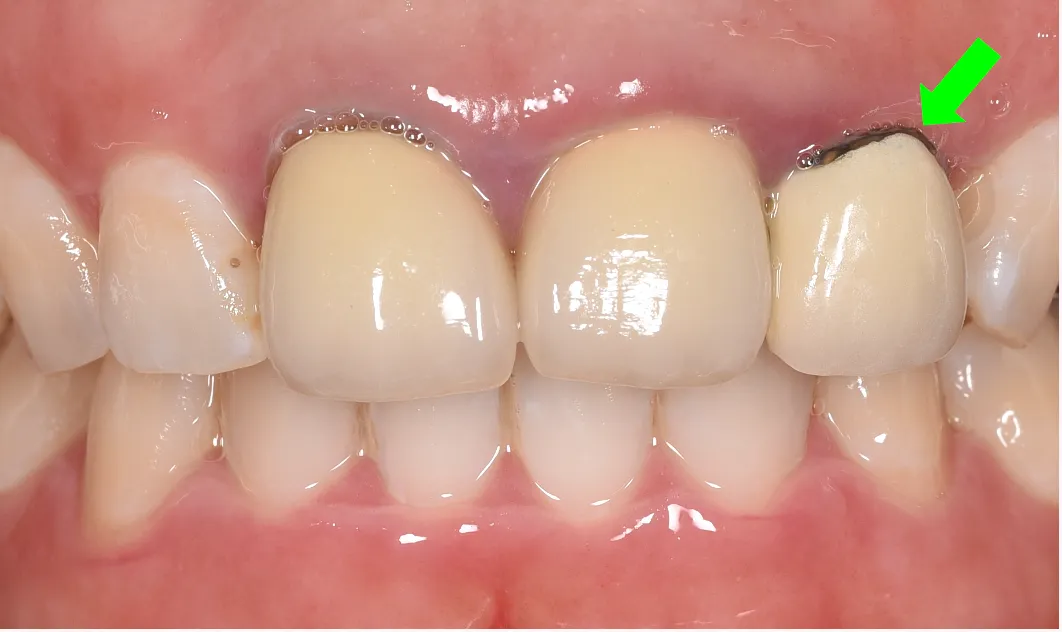

③メタルマージン

原因:

原因は2つ!

→メタルボンドと言われるセラミックの被せ物

→被せ物と歯の間に隙間が空いている -

撤去した被せ物

(メタルボンド)

表面は白い材料セラミックを使用していますが、

内側には金属のフレームが使用されています。

この金属のフレームの縁が黒く見える原因です。

メタルボンド

樹脂の仮歯

被せ物と歯の間に隙間が空いていると、そこの隙間から虫歯菌が入り込み黒くなります。 隙間が空かないように、即日入れた仮歯でも丁寧に治療を行えば隙間は空きません